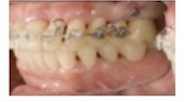

矯正治療と再生療法により骨欠損/歯周組織は改善され、インプラントによって動揺歯の負担は軽減された。

また、矯正によって歯軸傾斜が修正され、残存歯の合負担も減少した.

そのため、クロスアーチスプリントを回避でき、単冠/最小本数のブリッジでの補綴設計となった.

その結果、機能回復/審美性改善/残存組織の保全が得られ、治療再介入時も部分的な対応で可能となった.

4mm以上のPPDはなく,Bop(+)もなく、動揺も生理的範囲内で、何の問題も無く12年間経過している。

最終補綴物装着時(2007年9月)